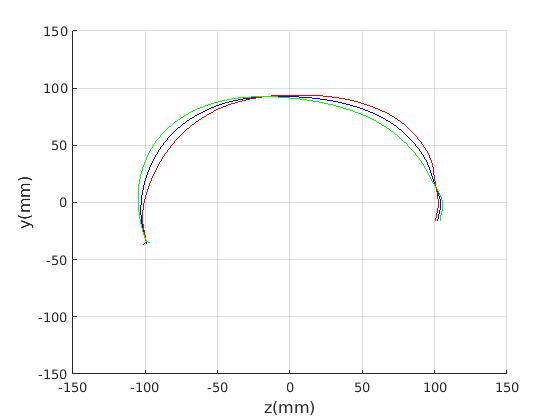

8 A case study of cranial profile model use for intervention outcome evaluation

In this section we take a sample of 25 boys, who are craniofacial craniosynostosis patients, 14 of which have undergone one type of corrective procedure (BS) and the other 11, another corrective procedure (TCR). Providing that the heads are sufficiently symmetrical and are amenable to ellipse fitting, we can parameterise all of these patients’ heads using our scale-normalised craniofacial profile model (2D model with face cropped out). We can then plot their pre-operative and post-operative parametrisations and compare them with the parameterisations of the 100 training examples. The expected result is that the parameterisations should show the head shapes moving nearer to the mean of the training examples. It also reveals which of the dominant modes of shape variation are most affected. The results are shown in figures 31 and 32.

For the TCR patient set, the Mahalanobis distance of the mean pre-op parameters (red triangle in Fig. 32) is 4.647, and for the mean post-op parameters (blue triangle) is 2.439. For shape parameter 2 only these figures are 4.354 and 2.439. We note that most of this change occurs in parameter 2, which corresponds to moving height in the cranium from the frontal part of the profile to the rear. In these figures we excluded one patient, who preoperatively already had a near-mean head shape (see red cross near to the origin in Fig. 32, so any operation is unlikely to improve on this (but intervention is required in order to relieve potentially damaging inter-cranial pressure).

It is not possible to make definitive statements relating to one method of intervention compared to another with these relatively small numbers of patients. However, the cranial profile model does show that both procedures on average, lead to a movement of head shape towards the mean of the training population. An example of analysis of intervention outcome for a BS patient is given in Fig. 33 and a TCR patient is given in Fig. 34. The particular example used is highlighted with circles on figures 31 and 32 to indicate pre-op and post-op parametrisations. To our knowledge this is the first use of statistical 3D craniofacial shape models in a clinical study.